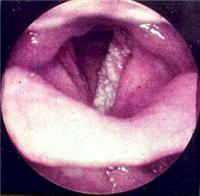

喉肿瘤的早期症状及预防

喉肿瘤的早期症状有哪些?喉肿瘤怎样早期发现预防呢?这里治疗喉肿瘤最专业的中医院介绍一下喉肿瘤的早期症状及预防,哪些人容易[详细]